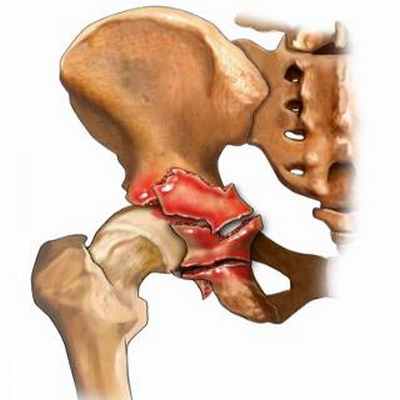

Вертлужная впадина расположена в месте соединения трех тазовых костей (седалищной, лобковой и подвздошной) и имеет форму полусферы. Ее центральная часть соединяется с головкой бедренной кости, образуя тазобедренный сустав. Различают свод или крышу, две стенки (переднюю и заднюю) и две колонны (переднюю и заднюю) вертлужной впадины. Колонны обеспечивают прочность данного анатомического образования и соединяются между собой в области свода, образуя перевернутую букву Y.

Все переломы вертлужной впадины в травматологии и ортопедии делятся на простые и сложные. Простые включают в себя поперечный перелом, перелом передней колонны, перелом передней стенки, перелом задней колонны и перелом задней стенки. При сложных повреждениях линия излома проходит через два или более элемента вертлужной впадины. К числу сложных переломов относят полные переломы обеих колонн, задний поперечный перелом в сочетании с повреждением задней колонны, Т-образный перелом, перелом задней стенки в сочетании с поперечным переломом, а также одновременный перелом задней стенки и задней колонны.

Рисунок 2. Рентгенограммы и МСКТ мужчины 39 лет. Автодорожная травма (удар в область левого вертела): вверху – при поступлении, комбинированный тип повреждения левой вертлужной впадины – неполный внутрисуставной перелом с поперечной линией излома, перелом задней стенки со смещением; внизу – после реконструкции и остеосинтеза поперечного перелома канюлированными винтами 7,3 мм, перелома задней стенки компрессирующими винтами 3,5 мм

Рисунок 3. Рентгенограммы и МСКТ мужчины 44 лет. Автодорожная травма (удар в область левого колена при столкновении): вверху – при поступлении, комбинированный тип повреждения левой вертлужной впадины – неполный внутрисуставной перелом с поперечной линией излома, оскольчатый перелом задней стенки с импакцией суставной поверхности (указано стрелкой) и смещением; внизу – после реконструкции и остеосинтеза переломов винтами и тазовыми пластинами 3,5 мм, с пластикой зоны дефекта препаратом искусственной кости «Хрон-Ос» (указано стрелкой)

Рисунок 4. Рентгенограммы и МСКТ мужчины 43 лет. Автодорожная травма (удар в область левого колена при столкновении): вверху – при поступлении, простой тип повреждения левой вертлужной впадины – оскольчатый перелом задней стенки со смещением отломков, вправленный вывих левого бедра; наличие свободного отломка в полости сустава, подвывих головки бедра; внизу – после реконструкции и остеосинтеза перелома задней стенки вертлужной впадины винтами и тазовой пластиной 3,5 мм